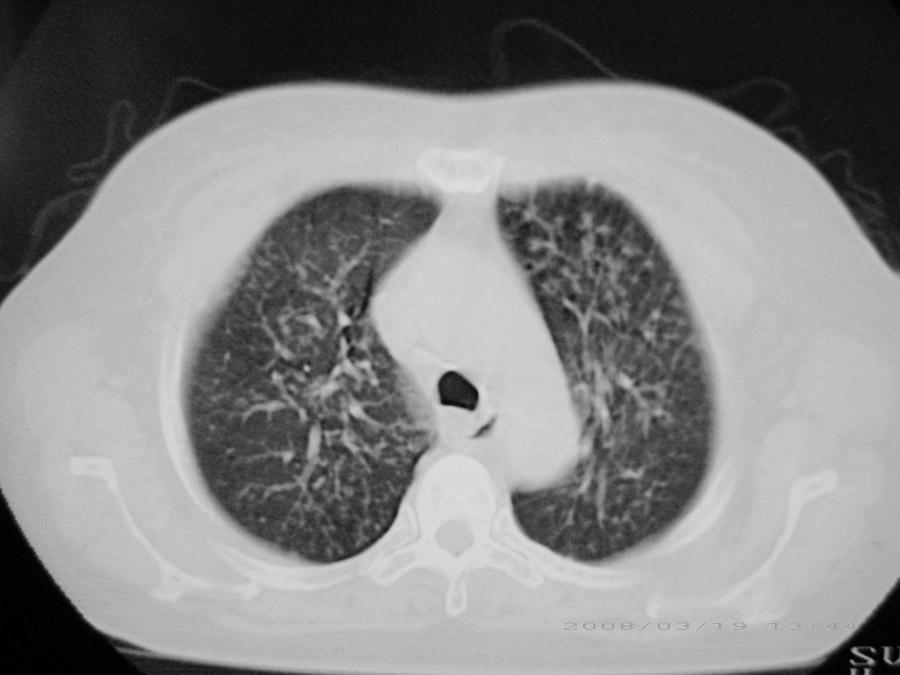

标题: CT13104:胸部大家看看啊,第一次发啊,

粟粒性结核

细支气管肺泡癌

本病例主要是癌性淋巴管炎与结节病的鉴别。好好查查吧。

密漫性沿纹理走行小结节影;有间质纤维化;可考虑尘肺;以图而论

血行播散性肺结核

两肺间质性病变!考虑间质纤维化?间质性肺炎!

双肺网状结构,小叶间质结节状增厚,考虑结节病

综合大家意见,结核、结节病、肺泡细胞癌均有可能,间质性肺炎暂不考虑,病灶纠集不明显,纵隔未见钙化淋巴结,尘肺可能性不大,但还是要密切结合临床诊断。

今天重新仔细看了看,矽肺确实不能除外,病灶主要表现为间质结节及纤维化。好好问问病史吧。